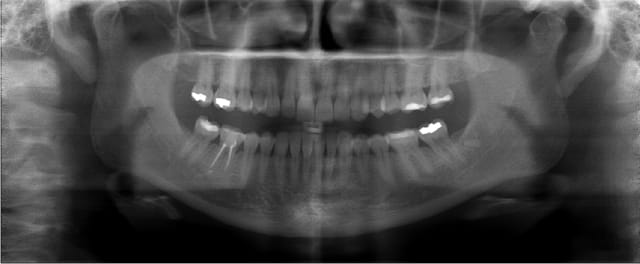

Bon finalement j'ai fait mon choix, cone beam installé hier !

Vatech Ewoo.

Pour moi les plus :

- taille de champ variable: 5*5 8*5 8*8 12.5*8

- vraie combo pano/cone beam

- interface sympa

- artefact métallique limité

- Logiciel d'imagerie et planification implantaire très bien

(pour info c'est une version d'Ondemand3D à l'essaie pour 90j ici:

http://www.ondemand3d.com/Content/Download/Trial.aspx prix du soft environ 5000$)

- budget compétitif

quelques clichés d'essais